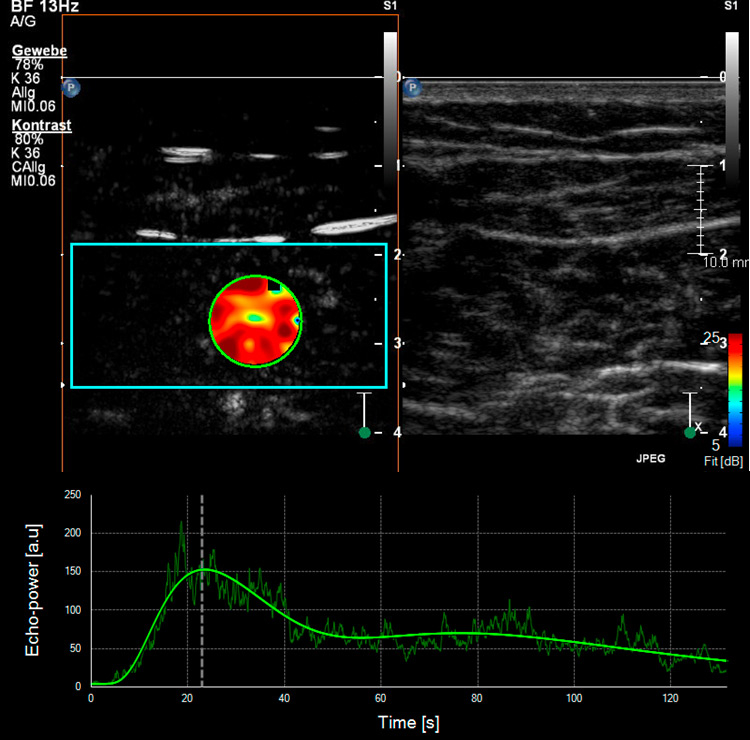

Figure 4

Skeletal muscle microperfusion on CEUS in a healthy volunteer (A) and a patient with peripheral artery disease (B). Corresponding time-intensity-curves of a region of interest (green circle) within the skeletal muscle (soleus muscle) after bolus injection of the ultrasound contrast agent with different shape in the healthy volunteer compared to the patient with peripheral artery disease.

Different studies have already used CEUS to analyse skeletal muscle perfusion in patients with PAD and with different cardiovascular risk factors (fig. 4). In one survey, the wash-in curves recorded in calf muscles of patients with symptomatic PAD showed an extended time to reach the maximum intensity as compared to healthy volunteers, and this was even more distinct in patients with reduced collateralisation and progressed disease [43, 44]. The time-to-peak intensity was significantly reduced after effective revascularisation by either percutaneous transluminal angioplasty or bypass surgery [45]. Another research group investigated calf muscle perfusion in symptomatic PAD patients at rest and during exercise (repetitive plantar flexion) by looking at the replenishment kinetics on harmonic power Doppler imaging. Patients with symptomatic PAD showed a significantly lower flow reserve when compared with normal volunteers [46]. Furthermore, the calculated muscle blood flow during exercise on CEUS imaging was impaired in the PAD subject group compared to the controls. By using dynamic CEUS, other investigators illustrated that the maximum signal intensity and the time to decline after temporary arterial occlusion (provoked at mid-thigh via inflatable cuff) were significantly affected in PAD patients [47]. By measuring the time-intensity curve in the muscle and the related arteries or veins selectively, patients with diabetes mellitus revealed a prolonged transit time of the microbubbles from artery to vein which in turn reflects a dysfunctional microcirculation [48, 49]. This was also shown in a similar way using CEUS perfusion imaging on the forearm flexor in patients with complicated advanced stage diabetes [50].